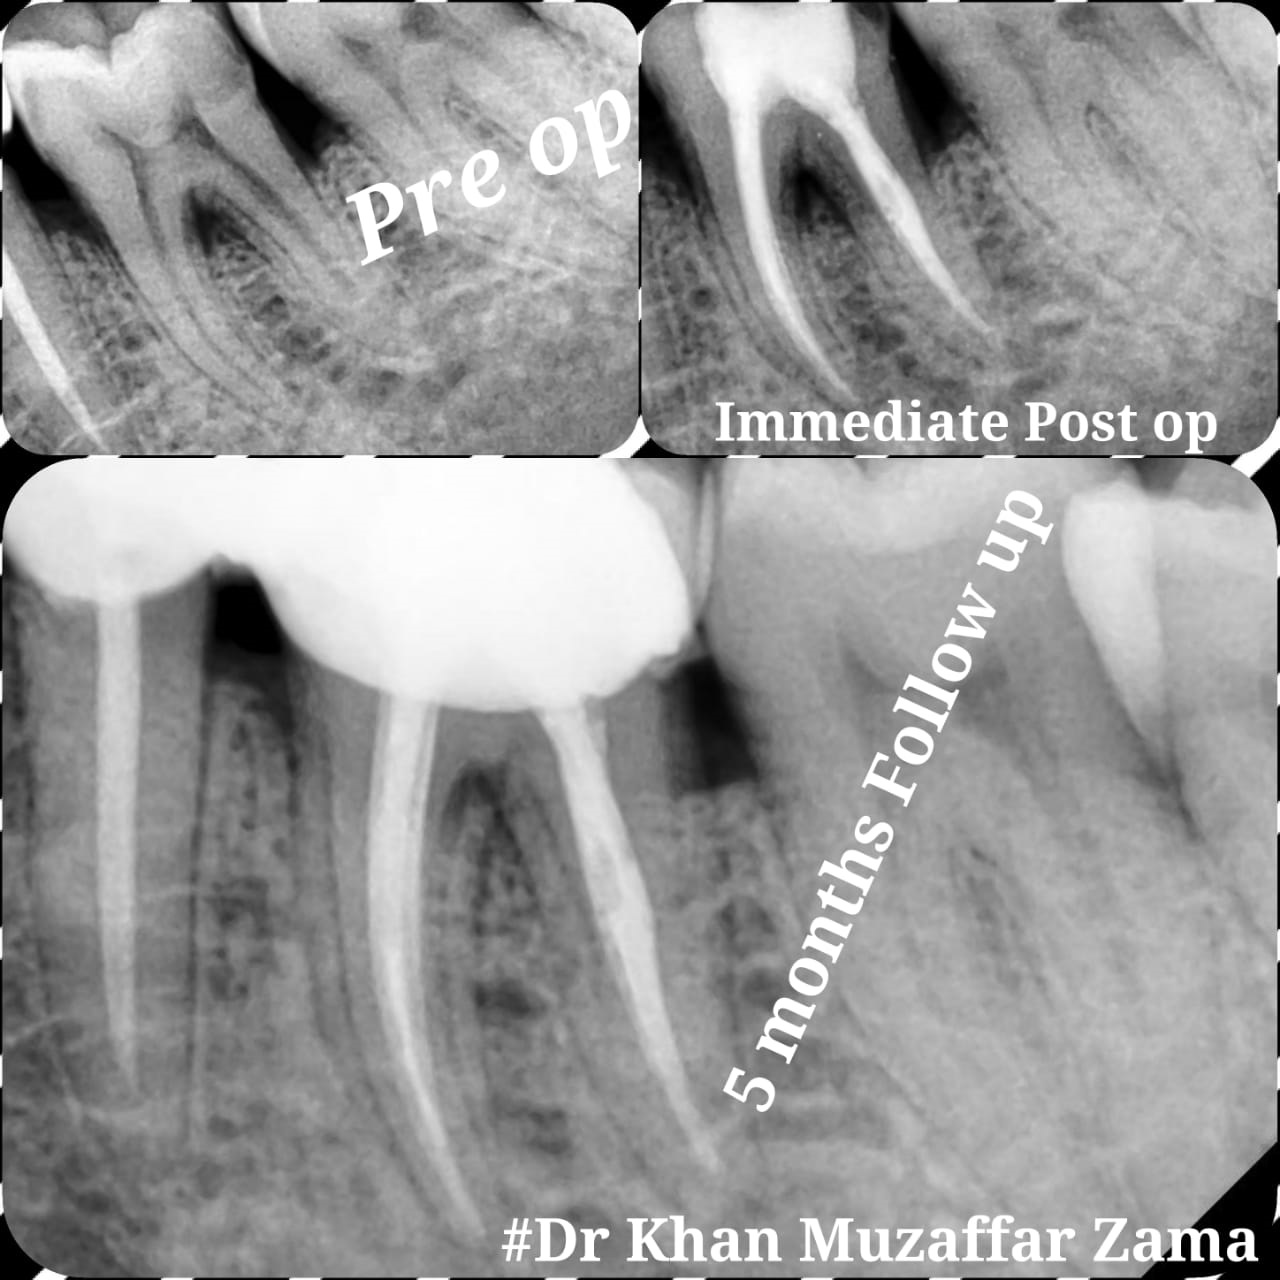

Cases